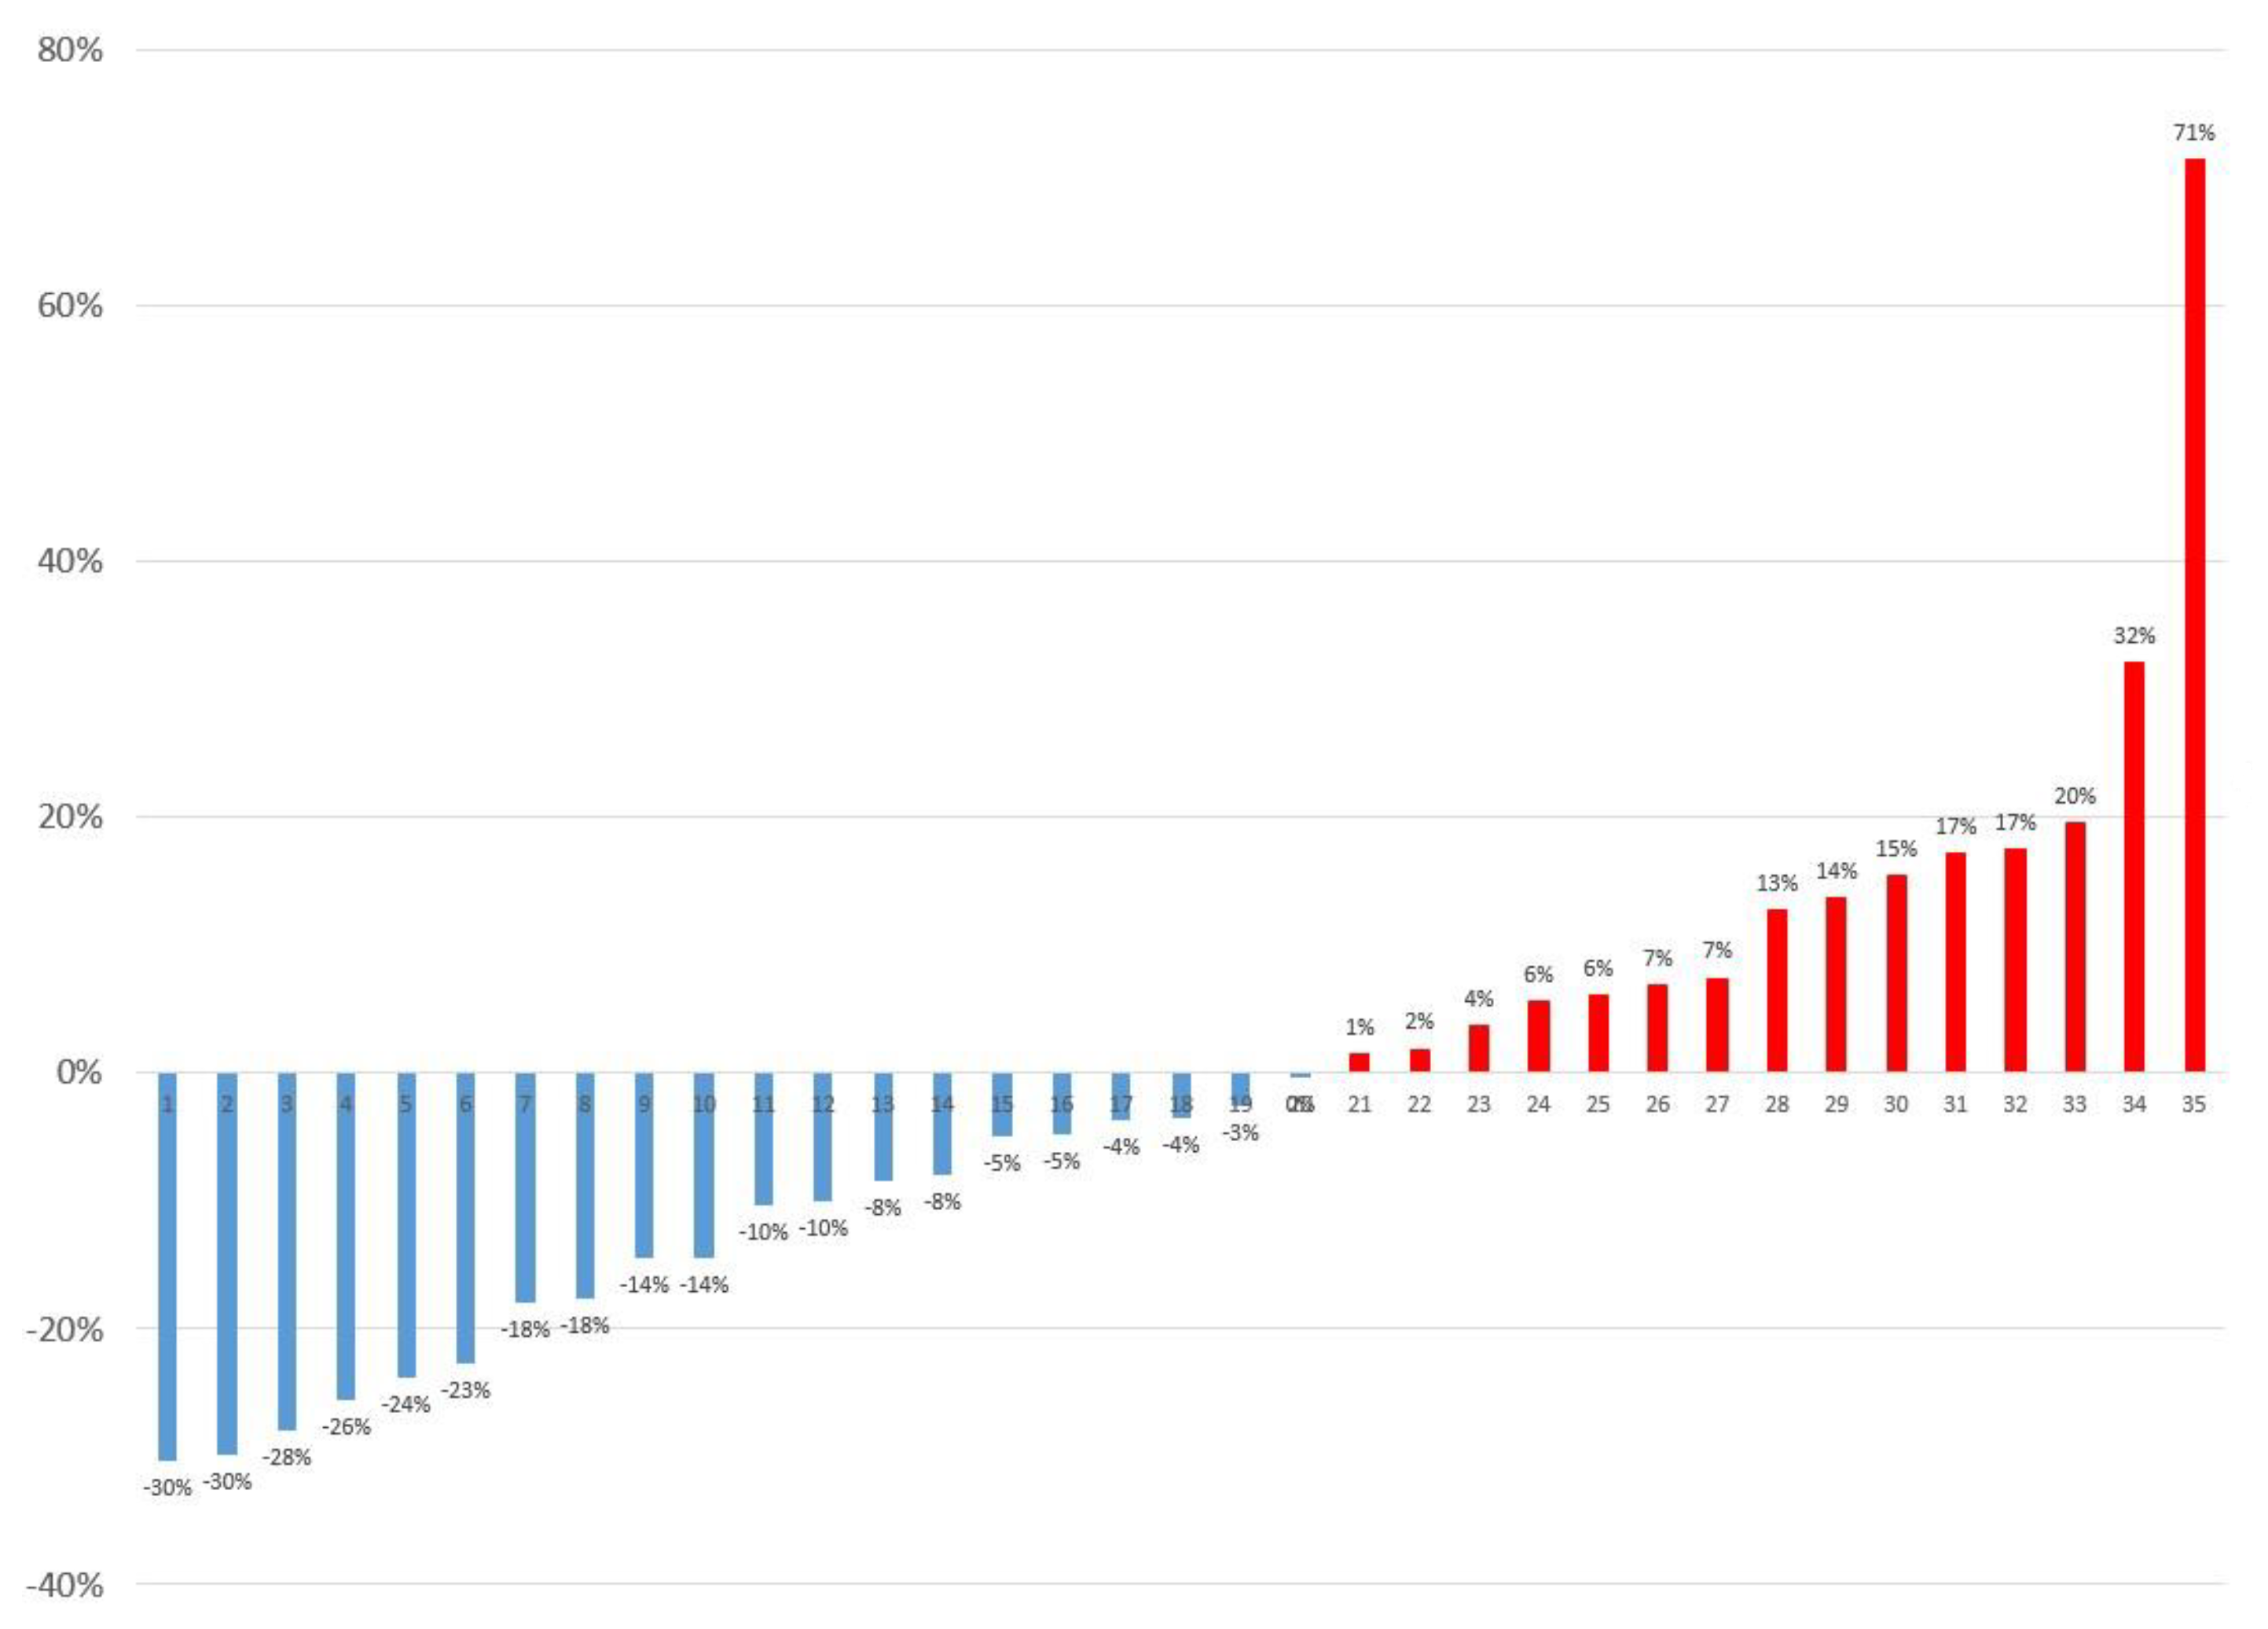

3. Results

| Parameters | Supine | Prone | p-Value |

|---|---|---|---|

| SUVmax, (mean ± SD) | 4.41 ± 2.05 | 4.23 ± 1.83 | 0.240 |

| MTV, cm3 (mean ± SD) | 5.83 ± 6.69 | 5.95 ± 6.24 | 0.672 |

| Location | |||

| Anterior, n (%) | 17 (49%) | 23 (66%) | 0.005 * |

| Middle, n (%) | 10 (29%) | 8 (23%) | |

| Posterior, n (%) | 8 (23%) | 4 (11%) |

| Reasons | Change of SUVmax (%) | n (%) | |

|---|---|---|---|

| Median | Range | ||

| [18F]FDG uptake outside the liver on CT in sPET/CT | 15% | [7% to 71%] | 4 (11%) |

| More blurring in sPET/CT | 11% | [−3% to 32%] | 6 (17%) |

| Unremarkable | 1% | [−8% to 18%] | 12 (34%) |

| More blurring in pPET/CT | −19% | [−30% to −8%] | 12 (34%) |

| [18F]FDG uptake outside the liver on CT in pPET/CT | −30% | [−30% to −30%] | 1 (3%) |

| Total patients | −4% | [−30% to 71%] | 35 (100%) |